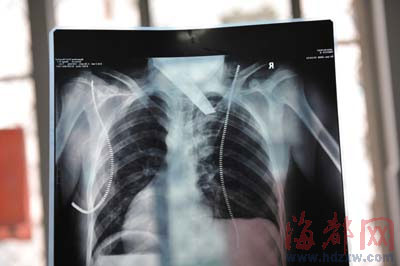

“求求你們了,一定要抓到兇手。”昨天下午,貴州人楊女士求民警幫忙。她17歲的兒子小勇,前天在網(wǎng)吧被前工友捅了兩刀,最后一刀從后背插進(jìn)胸膛,傷及肺部。醫(yī)院搶救了4個(gè)小時(shí)后,才取出匕首,隨后又切除部分受傷的肺,小勇才醒了過(guò)來(lái),但仍未脫險(xiǎn)。

前晚,在第一醫(yī)院急救室,經(jīng)過(guò)4個(gè)多小時(shí)的搶救,醫(yī)生將匕首從小勇身上取出,發(fā)現(xiàn)這把匕首的刀尖扎斷了1厘米。由于小勇肺部被刺中,昨天上午,醫(yī)生再次進(jìn)行了3個(gè)多小時(shí)的手術(shù),切除了受傷的部分肺,直到下午,小勇才挺過(guò)來(lái)!巴α艘灰,現(xiàn)在總算醒了過(guò)來(lái)!睏钆恳灰箾](méi)睡,守在手術(shù)室外7個(gè)多小時(shí),生怕兒子再醒不過(guò)來(lái)。不過(guò),由于傷勢(shì)嚴(yán)重,小勇目前戴著氧氣呼吸,仍未脫險(xiǎn)。